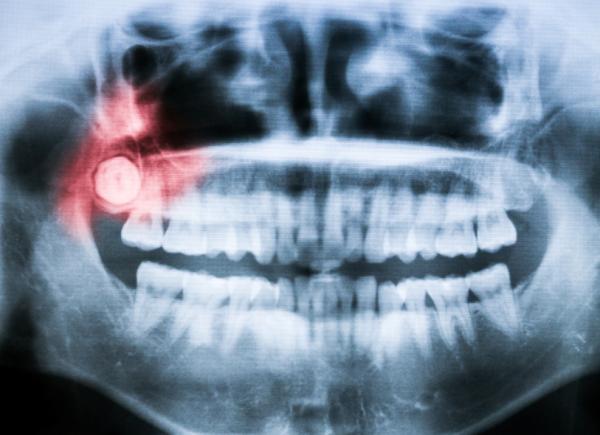

La pericoronaritis hace referencia a un trastorno dental en el cual los tejidos de la encía que rodean un diente parcialmente erupcionado se inflaman y se infectan, ocasionando dolores y molestias que pueden incluso complicar acciones tan simples como comer, tragar o abrir y cerrar la boca. Generalmente, sucede en las cordales, más conocidas popularmente como muelas del juicio, cuando no tienen el espacio suficiente para salir o se encuentran mal posicionadas. En todos los casos, será conveniente acudir al odontólogo para poder solucionar el problema y evitar mayores complicaciones que pongan en grave peligro la salud bucodental. En este artículo de unComo mostramos con detalle cómo tratar la pericoronaritis, así como sus causas y síntomas frecuentes.

La pericoronaritis sucede, como hemos mencionado, cuando la encía que hay alrededor de una pieza dental parcialmente erupcionada se inflama y se infecta debido a una proliferación bacteriana, algo que puede ocurrir en cualquier diente pero que se da frecuentemente en las muelas del juicio, y es que en muchos casos estas no disponen del espacio suficiente para salir y quedan cubiertas de manera parcial por la encía.

Por otro lado, en aquellos casos en los que los cordales o muelas del juicio no cuenten con el espacio suficiente para erupcionar de forma adecuada o no estén bien posicionadas, se deberán extraer para evitar problemas dentales más graves y padecer de pericoronaritis en futuras ocasiones.